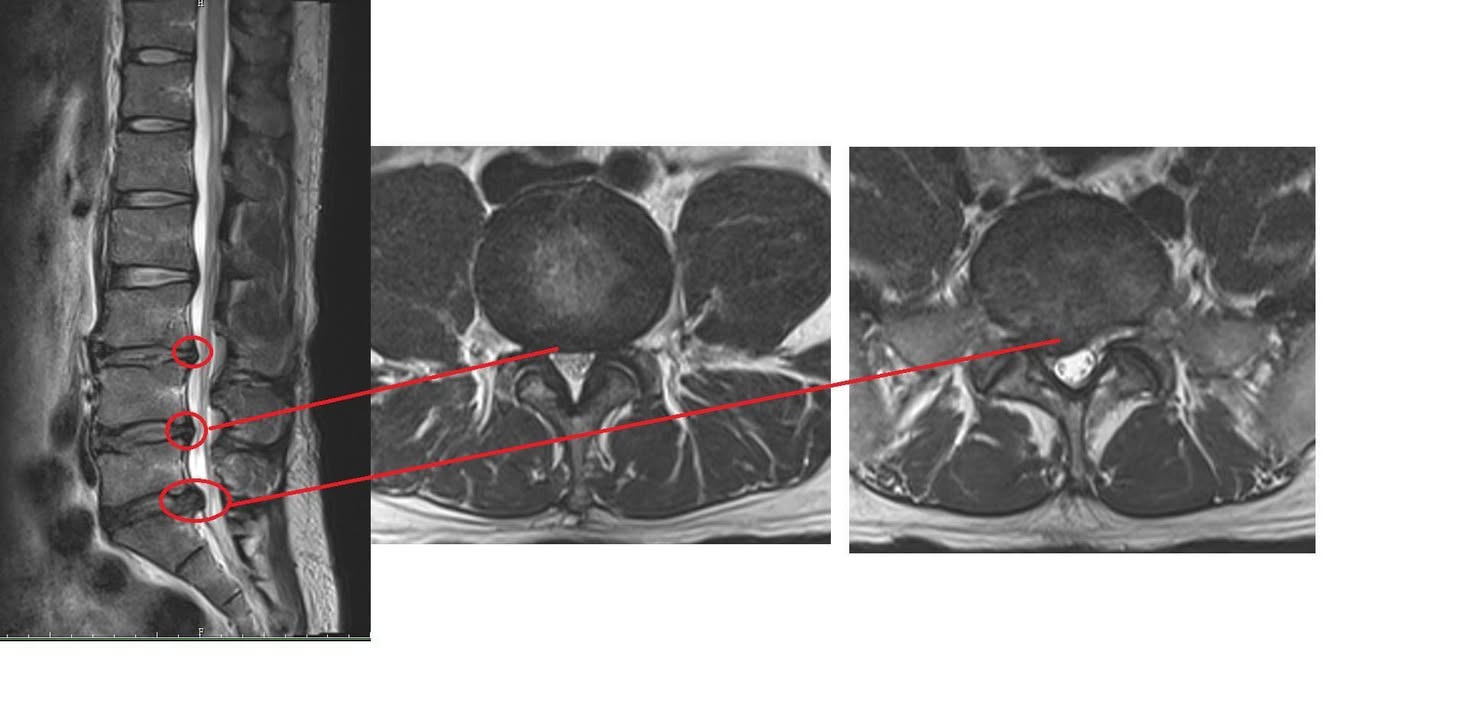

Cervical Spine Treatment Cases 腰椎治療案例 #今天來聊巨大骨刺為何可以吸收回去! #椎間盤突出需要多久才能吸收呢? #馬尾神經症候... 2020.09.08 #典型假性坐骨神經痛 #原來是梨狀肌症候群 #核磁共振排除椎間盤突出 #抽絲剝繭真相大... 2020.08.13 #嚴重椎管狹窄醫案 #感謝台北林大哥熱情見證 #從寸步難行到輕快漫步 #鍛鍊多裂肌的重... 2020.08.12 #椎間盤突出可以吸收回去嗎 #微針治療原理是什麼 #何時一定要接受神外開刀 #一張圖秒... 2020.08.11 #感謝花蓮鄉親林大姐熱情見證 #一分鐘認識椎管狹窄 #原本痛到無法走路打算開刀了 #脊... 2020.08.01 #感謝新莊區林先生熱情見證 #椎間盤突出跟纖維環裂隙的關係 #纖維環破裂突出可以不... 2020.07.28 #逆轉勝又一發case #原本疼痛一年多想說一定要手術治療了 #八週治療後症狀全部消失 #... 2020.07.25 #巨大椎間盤突出一定要開刀嗎 #除了開刀以外的選擇 #感謝台北市吳先生熱情見證 2020.07.24 #腰椎滑脫的疼痛心酸誰人知啊 #一分鐘瞭解腰椎滑脫 #哪一種情況需要積極開刀 #要如何... 2020.07.21 #巨大椎間盤脫垂一定要開刀嗎? #感謝新店林先生熱情見證受訪 #西醫手術有那些選擇... 2020.07.02 #纖維環裂隙AnnularFssures #MRI看起來不嚴重卻嚴重困擾患者 #感謝桃園市蕭先生熱情見... 2020.06.19 #骨刺有可能吸收回去嗎?? #疼痛超過六年的特殊案例探討 #MRI核磁共振前後對比 #感謝... 2020.06.14 #坐骨神經痛一定要開刀嗎 #突出的骨刺真的可以自己吸收嗎 #最新英國醫學期刊BMJ的看... 2020.05.30 #骨刺跟突出髓核有可能吸收回去嗎?? #特殊案例探討 #核磁共振一年後對比 2020.05.29 #從醫以來第一次碰到薦椎Tarlov cyst囊腫#左邊紅色圈圈是個案,右邊是國外案例#腰... 2020.05.23 ← 上一頁 10 11 12 13 14 下一頁 →